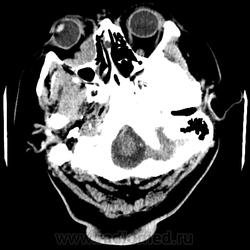

Женщина 48 лет, поступила с подозрением не ОНМК. На КТ -данных за ОНМК не обнаружено, но в правой орбите ретробульбарно мягкотканное образование +45HU, признаков деструкции и ремоделирования костных структур орбиты не наблюдается, медиальная и нижняя прямая мышца отчетливо не дифференцируются, зрительный нерв тесно прилежит к данному образованию. После КУ гомогенное накопление КВ и повышение плотности до +65HU. Экзофтальм. Жалобы на снижение зрения. Год назад делала МРТ ГМ, на снимке патологии орбит не увидел. Идиопатическая псевдоопухоль орбиты?

В мягких тканях носогубного треугольника справа тоже образование.

Натив

Контраст

На первое место все же поставила бы гемангиому. Локализация, возраст, пол, флеболит, случайная находка, безболезненный экзофтальм, ремоделирование стенок орбиты -это за гемангиому.

Кавернозная гемангиома? Ремоделирования стенок орбиты как раз таки нет, они интактны. Должна быть псевдокапсула, а здесь больше похоже на инфильтрацию прямых мышц, я за псевдоопухоль.